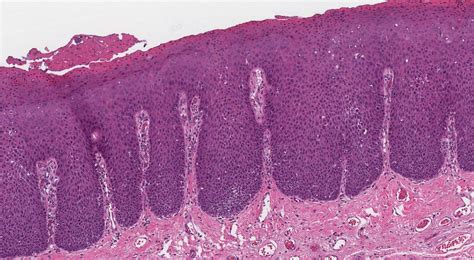

HPV in Mouth Pictures: What They Can Reveal

HPV in mouth pictures can provide valuable insights into the appearance and location of oral warts. These pictures can help healthcare professionals diagnose the condition and determine the best course of treatment. However, it's important to note that visual examination alone is not sufficient for a definitive diagnosis. Additional tests, such as a biopsy or HPV DNA test, may be required to confirm the presence of the virus.

Here are some key points to consider when examining HPV in mouth pictures:

• Appearance: Oral warts can appear as small, flesh-colored or white growths on the lips, tongue, or inside the cheeks. They may be flat or raised and can vary in size and shape.

• Location: Oral warts can occur in various locations within the mouth, including the lips, tongue, gums, and inner cheeks. The location of the warts can provide clues about the type of HPV and the potential risk of complications.

• Symptoms: While oral warts are often painless, they can cause discomfort during eating or speaking. In some cases, they may be accompanied by other symptoms such as sore throat, difficulty swallowing, or swollen lymph nodes.